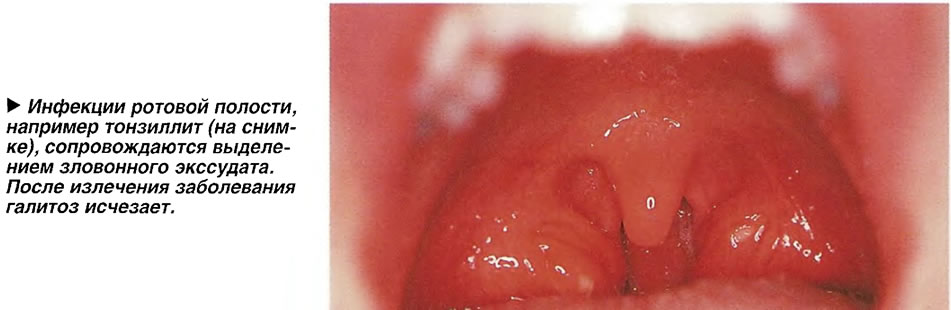

Острый тонзиллит и фарингит, вызывающие сильные боли в горле, сопровождаются также выделением зловонного экссудата, который стекает по задней стенке глотки. После излечения болезни дурной запах изо рта исчезает.